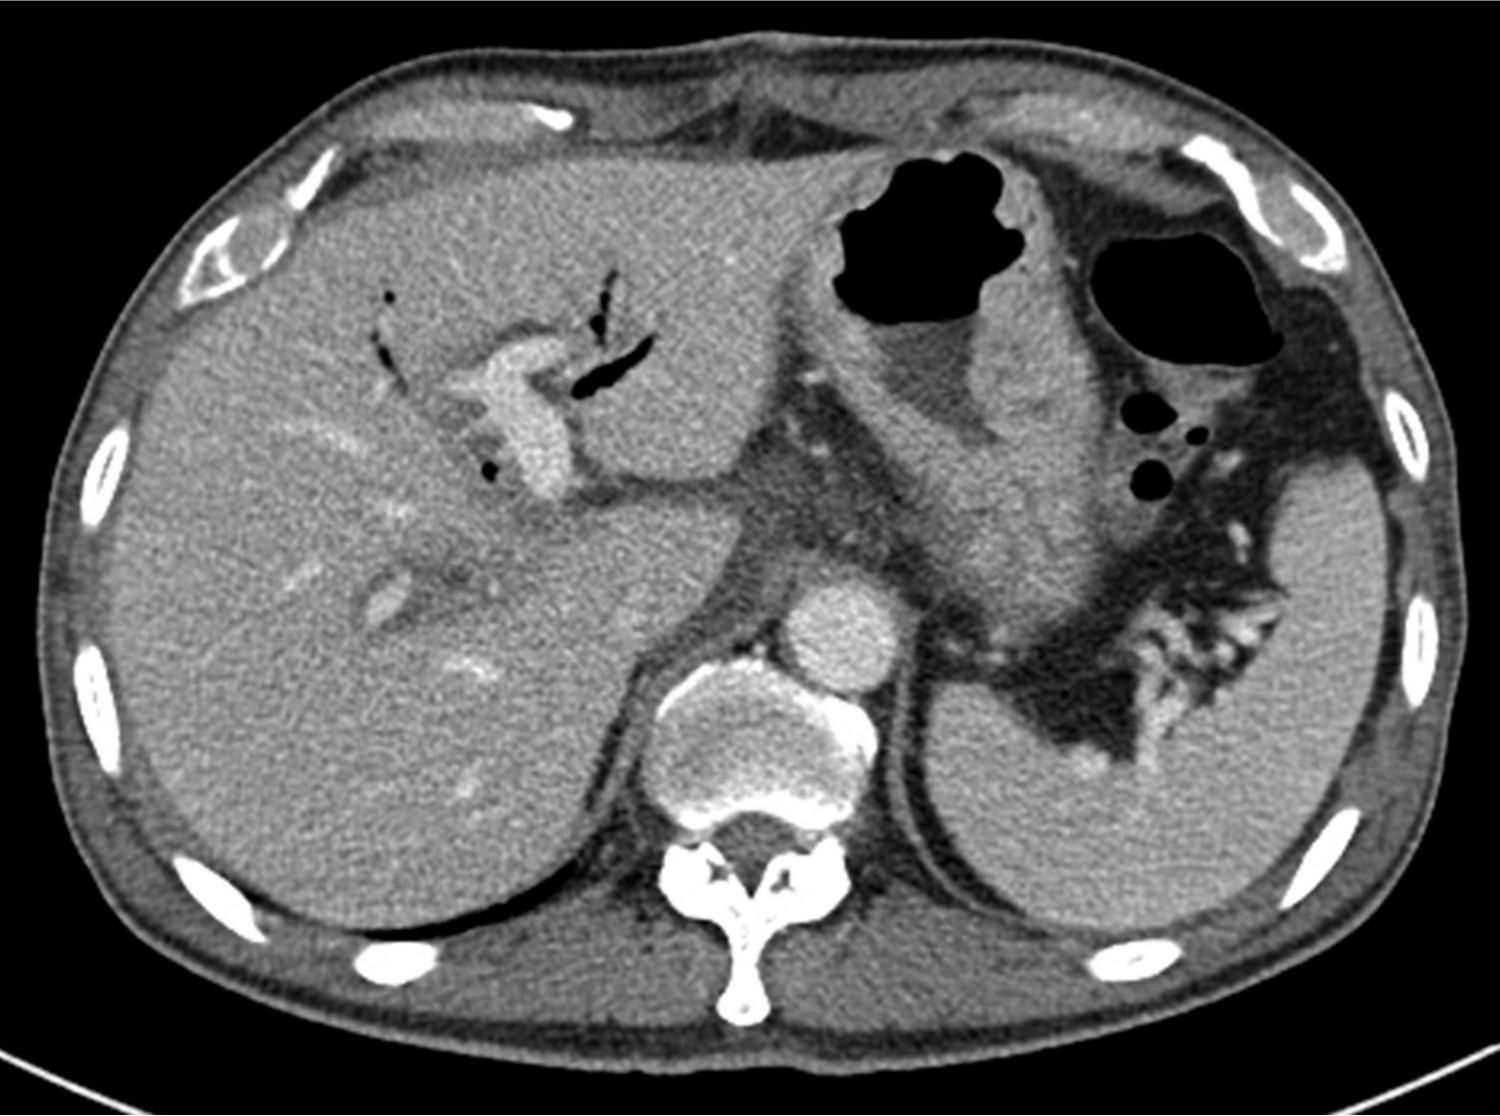

총담관과 간문맥 분절 절제 및 루엥Y 간공장문합술 시행 3일 후 촬영한 간 도플러 초음파에서 문맥의 혈류가 관찰되지 않았으며 주문맥을 비롯하여 양측 문맥에 동일에코의 결절들이 있어 혈전증으로 생각되었음. CT에서도 주문맥이 혈전에 의해 폐쇄되어 있어 원위부 문맥 혈류가 보이지 않았음(Fig. 1).

Fig. 1. A

Figure 1. Contrast-enhanced CT scan following segmental resection of bile duct with Roux-en-Y hepaticojejunostomy and segmental resection of portal vein with end-to-end anastomosis. Both axial (A) and coronal (B) studies show a thrombus (arrows) in the narrowed main portal vein and peripheral portal flow is not seen.